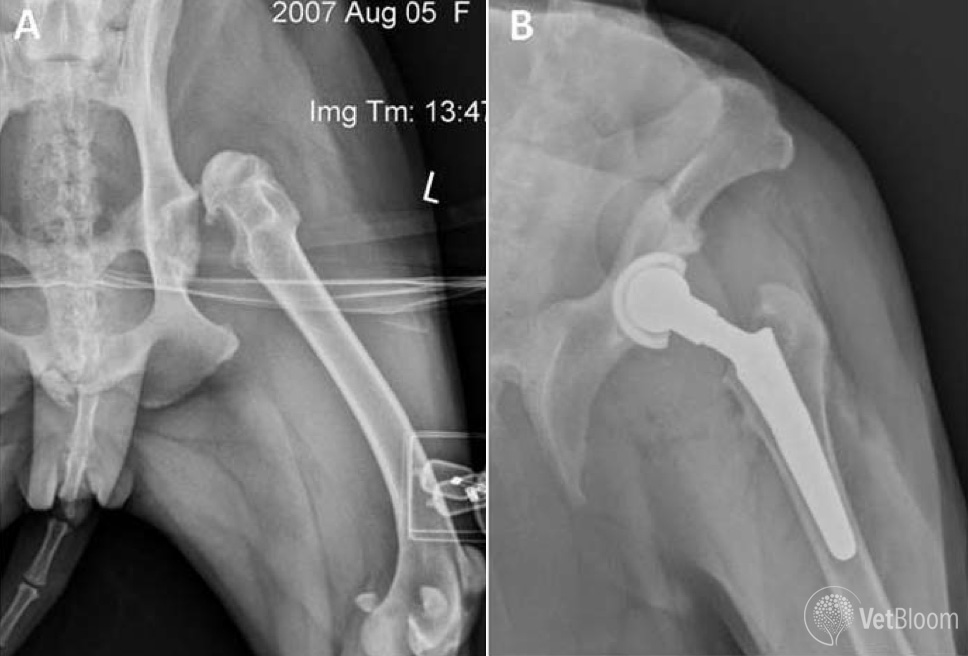

From blog.vetbloom.com